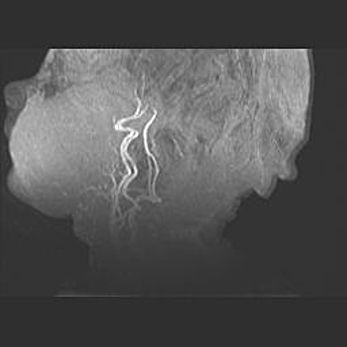

Подострая гематома правой гемисферы мозжечка.

Наружная гидроцефалия.

Возраст: 15 дней

Вес: 3100 г

Пол: женский

Окружность головы: 37 см

Срок гестации: 35-36 недель

При открытой наружной форме гидроцефалии у новорожденных расширяются и переполняются субарахноидные пространства.

Кровоизлияния в мозжечок имеют две клинико-анатомические формы: полушарные гематомы и кровоизлияния в червь.

К появлению этой патологии может привести: повреждения головного мозга, возникающие в результате асфиксии и гипоксии плода при беременности, или травмы во время родов. Редко гематома мозжечка может быть результатом первичной коагулопатии и сосудистой мальформации, диссеминированном внутрисосудистом свертывании, изоиммунной тромбоцитопении.